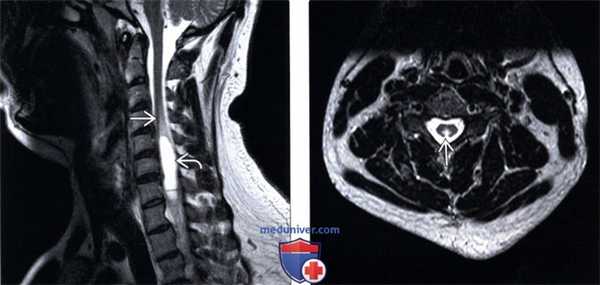

(Слева) Сагиттальный срез, Т2-ВИ, пациент с ПКД на фоне недостаточности меди: отмечается линейная гиперинтенсивность сигнала задних отделов шейного отдела спинного мозга. Миелопатия вследствие недостаточности меди является одной из курабельных причин некомпрессионной миелопатии и очень напоминает ПКД вследствие недостаточности витамина В12.

(Справа) Аксиальный срез, Т2-ВИ: фокальная гиперинтенсивность задних столбов спинного мозга вследствие ПКД у пациента с гипокупремией.